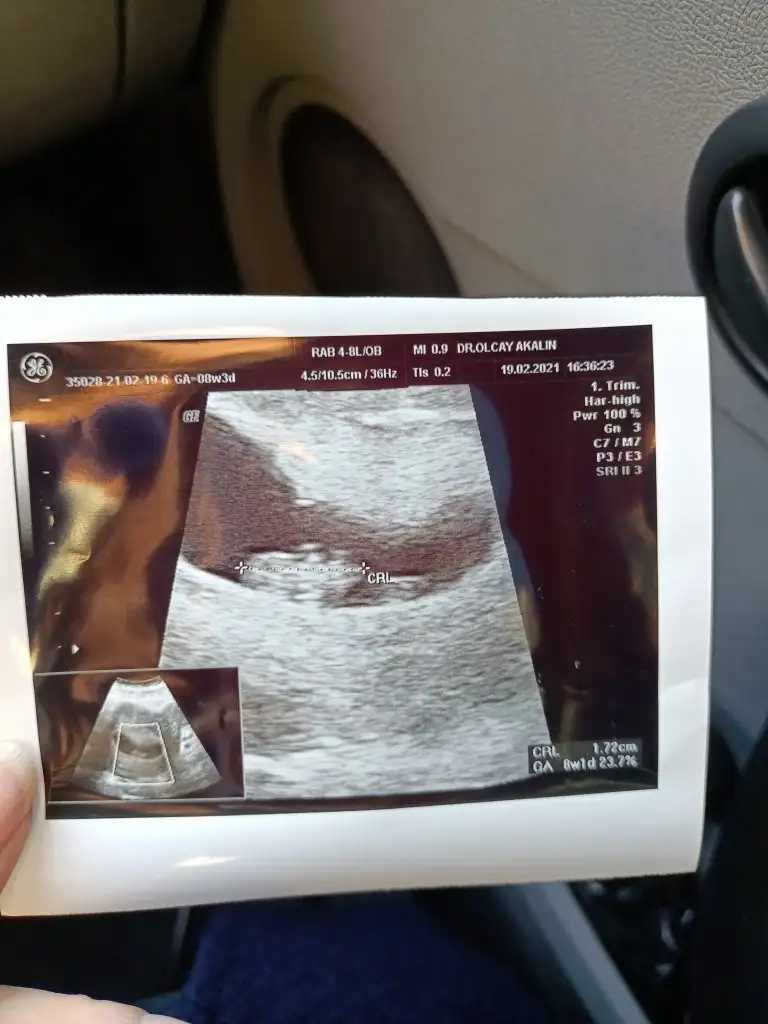

Kiz diyorumBenimkine de bakar mısınız

Merhabaaa benimkine de bakar mısınız acaba 8+1Kiz diyorum